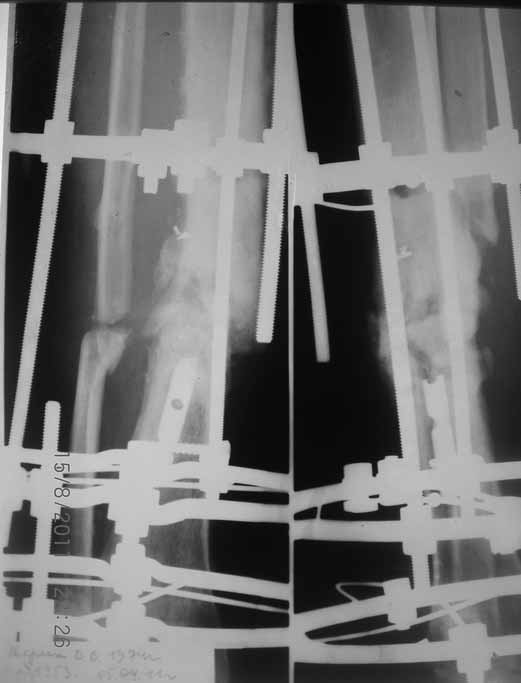

Это гипотрофический ложный сустав. Проблем видится несколько:

1. нарушение трофики в месте перелома.

2. после фиксации в аппарате Илизарова на рентгеногнрамме имеются признаки спицевого остеомиелила. В настоящи момент хотя свищей нет с мая 2011 нет опасно ли фиксировать голень стержнем?

На основании каких признаков Вы решили, что кость мертвая! Имеется гиперпластический ложный сустав, как результат недостаточно стабильной фиксации ан предыдущих этапах лечения. В данном случае необходимо решение следующих вопросов:

1 наличие инфекция в зоне ложного сустава

2. коррекция оси

3. окончательная стабильная фиксация

4. исключение предыдущих ошибок

5. оценка своих возможностей.